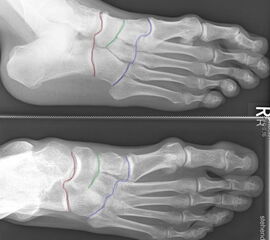

Unter den Mittelfußbereich fällt die Lisfranc- (blau), die Bona-Jäger- (grün) und Chopart- (rot) Gelenkreihe

Die Lisfranc-Gelenkreihe wird aus den Ossa cuneiformia/Os cuboideum und den jeweiligen Metatarsalia gebildet. Die Bona-Jäger-Gelenkreihe liegt zwischen dem Os naviculare und den Ossa cuneiformia. Die Chopart-Gelenkreihe wird aus Talus/Calcaneus und Os naviculare/Os cuboideum gebildet. Vor allem ist die Lisfranc-Gelenk-Linie von degenerativen Veränderungen betroffen, hierbei häufiger die mediale Säule, also die Tarsometatarsal-Gelenke I-III.